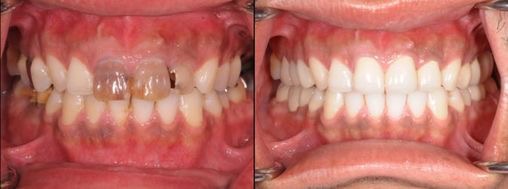

歯周病治療前と治療後の比較